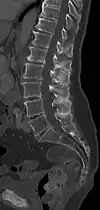

Baastrup's sign is an orthopedic and radiographic disorder that often occurs in elderly humans. It is characterized by enlargement of the posterior spinous processes of the lumbar spine, with normal intervertebral disc height and neuroforamina. The reason it is referred to as kissing spine is because the posterior spinous processes 'kiss' and touch one another as the individual goes into lumbar extension, for example when flat on their stomach.[1][2] The condition has been seen in humans, canines, particularly with boxer breeds,[3] and certain breeds of horses.[4] This disorder is named after Christian Ingerslev Baastrup.

| A diagram of a human vertebral body. With Baastrup's sign, the posterior spinous process, pointing down and to the left, is abnormally thickened due to repetitive microtrauma. | |

The salient feature of the disorder is the exuberant osteophytosis that occurs at posterior lumbar spinous processes. Osteophytes are coarse calcifications at the edges of bone that form due to repetitive stress and trauma. There is also atrophy and fatty replacement of paraspinal musculature, which can be detected by CT or MRI.[5]